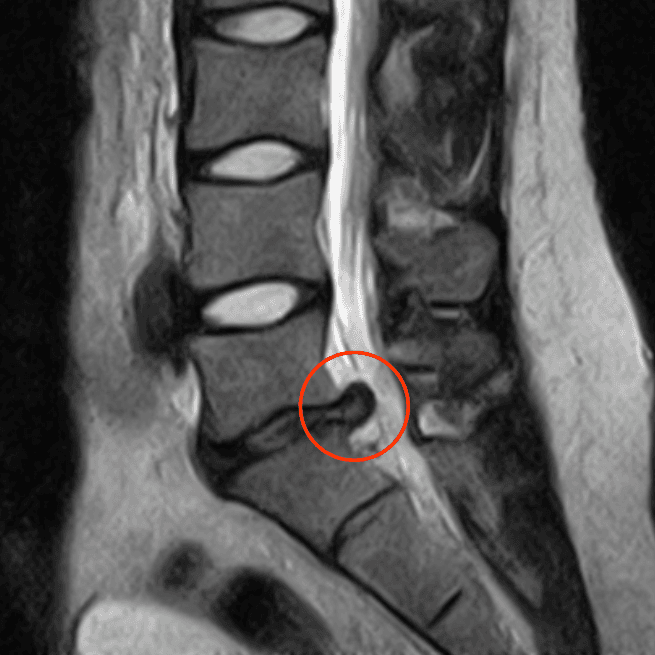

Sur les comptes rendus médicaux, vous pouvez lire le terme discopathie, qui signifie simplement une atteinte du disque intervertébral. Pour des atteintes plus spécifiques, on parlera d'hernie discale (déformation en forme de doigt de gant) et de protrusion discale (bombement du disque).

Les symptômes les plus courants sont des douleurs au bas du dos et une sciatique (irradiation dans la jambe) pour une hernie lombaire. Pour une hernie cervicale, les symptômes incluent des douleurs au cou et une névralgie cervico-brachiale (irradiation dans le bras).